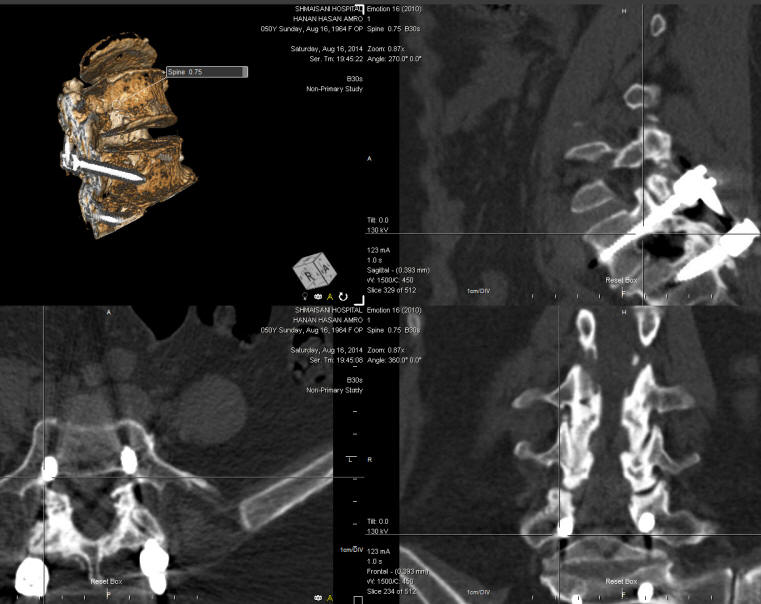

26-AUGUST-2014  HANAN HASAN AMRO  50 YEARS  RESIDUAL AFTER TRANSPEDICULAR FIXATION L5-S1 WITH RIGHT SCIATICA.

The patient came to the clinic 16-August-2014 complaining of right sciatica for 4 months. She was operated 3 years ago for spondylolisthesis in Saudi Arabia 3 years ago, after what the patient telling that she improved for 60% approximately, but deteriorated the last 4 months.

On examination; the patient is in agonizing pain, limping with exaggerated scoliotic stance. SLRS was 40 degrees in the right with pain and 70 degrees with less pain. There is weak dorsiflexion right foot -3/5 and planterflexion same foot 4/5. There is hypalgesia right S1 root territory.

The patient was sent for new MRI of the lumbar spine with dynamic studies and CT-scan of the operated area and lab investigations. The CT-scan with reconstruction using ORS Visual showed the right upper screw touching the root. It was decided to explore the the site of surgery and resolve all her problems.

The old incision refreshed and the four screws exposed. The right rod was removed. Using Inomed ISIS transpedicular screw protocol, the right lower screw and both left screws did not gave EMG response even with 15 mA DNS stimulation. The right upper screw gave response even with 8 mA DNS stimulation. The construct is of Expedium brand. The type of the screw is polyaxial. It was removed and inspection of the screw cavity with feeler confirmed that it is located in the soft tissues. As seen in the figure below, the screw was inserted vertical to the sagittal plan and it was media at the level of the pedicle and outside the body of the L5. Foraminotomy right L5  and S1 roots. They were responding even with 1-2 mA DNS stimulation. Using Stryker XIA 3 system a new polyaxial screw 6.5x50 mm was inserted from near upper point and directed medially. All the screws now not responding even with 15 mA DNS stimulation. MAC cross connector 42 mm was applied to gain more stability of the construct. The harvested bone melt and applied lateral to the rods. Routine closure of the wound.

Smooth postoperative recovery with normalization of the power of the right foot.

The patient is a difficult case to estimate. Only with use of special software such as ORS Visual explained the real wrong position of the screw.

CT-scan reformatted using ORS Visual showing wrong direction of the right upper screw.